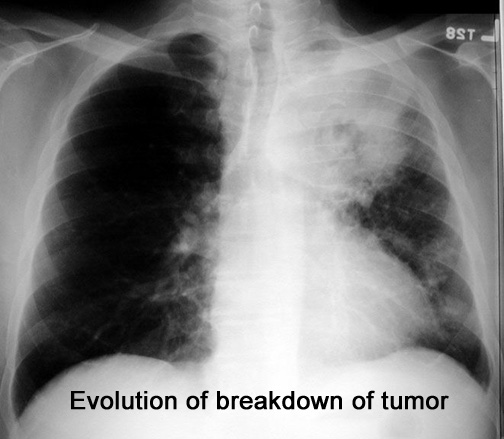

Case 12 Labeled Image

Labeled Image

Follow the progression of break down of tumor. What are stalactites and stalagmites?